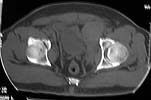

To recap: Middle aged male patient on whom a heavy log fell and sustained injury. Had pelvic ring disruption with fracture femur. Ext fix of pelvis and interlocking nailing of femur done. Developed compartment syndrome thigh and had fasciotomy. Went on to rhabdomyolysis and ARDS. Managed with ventillation and alkalinising. Fasciotomy wound later skin grafted.

Now what I have not told so far: At about three weeks after the injury when patient had recovered from the problems described above developed acalculous cholecystitis. As he was being prepared for surgery he suddenely collapsed and went into shock. Required resuscitation and inotropic support. After vital signs were stable he was taken up for laparoscopic cholecystectomy. On introducing the scope it was found that there was a gangrenous gall bladder with lots of inflammation all around. It was converted to an open cholecystectomy. Ventillated post op. Patient's ext fix on pelvis was removed after six weeks and ambulated with walker. Had developed a deep sacral pressure sore. Discharged with home care of pressure sore and ambulation with support. Now at about three weeks the femur is uniting, pelvis stable and the pressure sore healing. Patient changed to axillary crutches from walker.

My question to the list: How often do you see acalculous cholecystitis following pelvic fracture? Any other comments?? Laparoscopic picture of gall bladder and present x-rays attached.